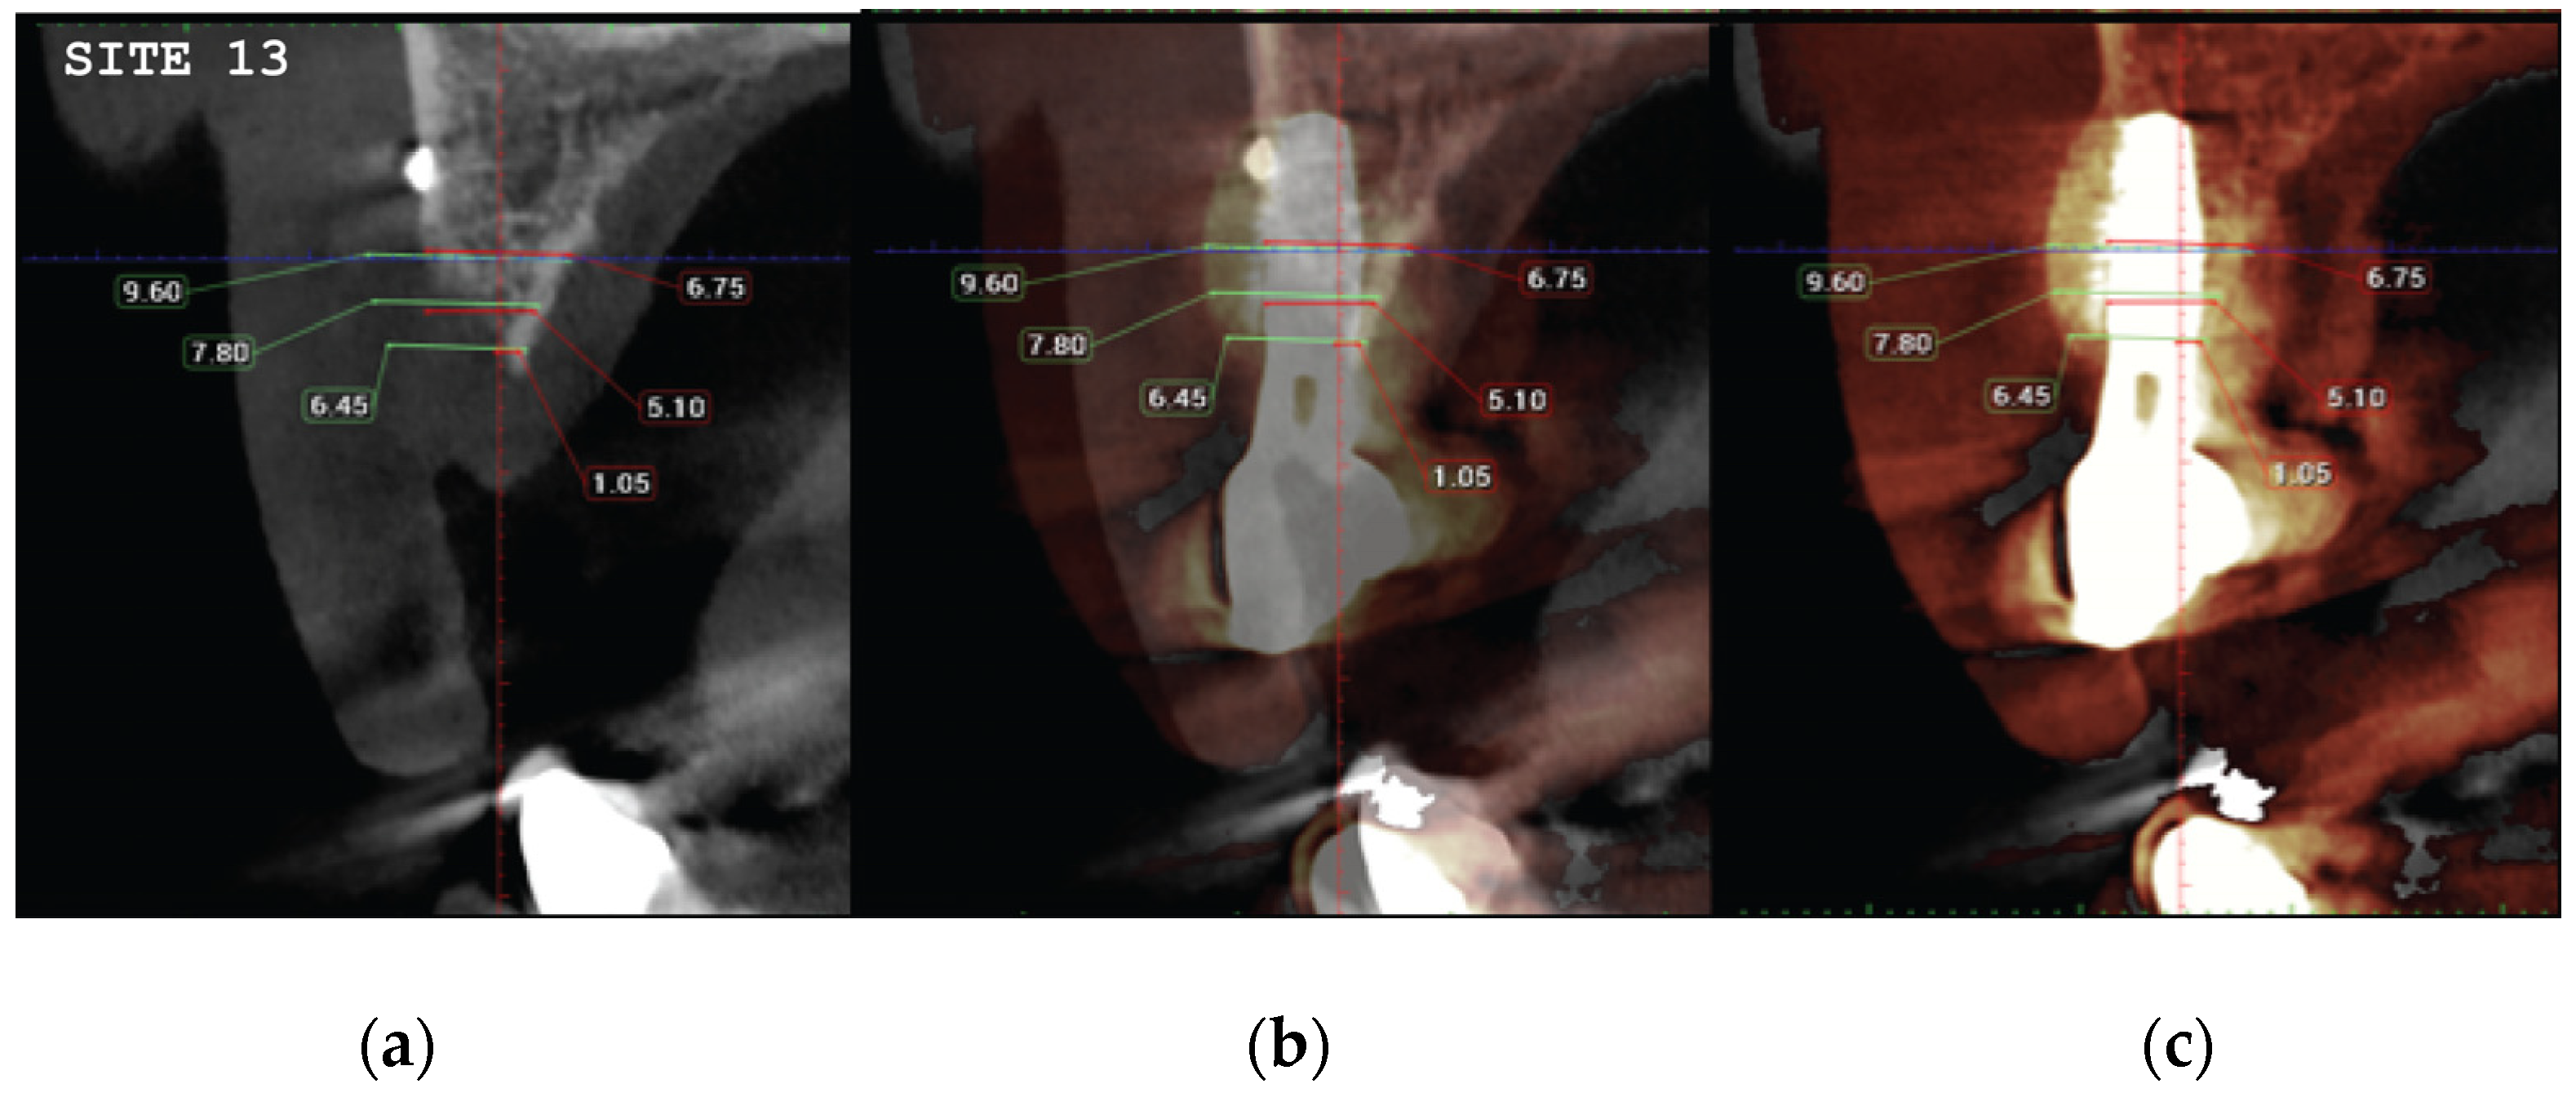

Data Collection

CBCT images were obtained using a CS8100 3D Carestream computed radiography system (Carestream Health, USA), at 0,150mm voxel size and field of view 8x9 cm prior (T1) and 16 weeks (T2) after implant placement. The original files in -DICOM format- were imported into the Romexis software (Planmeca Oy, Tuusula, Finland) for analysis. Both T1 and T2 datasets were superimposed in the software, using a point-based registration and if needed further manual alignment by an experienced oral imaging specialist. 2D measurements were acquired on both registered volumes where a slider tool could help hide and show the second superposed volume. First, measurements on T1 were done, after on T2. The cross-section in the middle of the site on the axial slice, and perpendicular to the alveolar crest was used to measure alveolar widths at 1mm, 3mm and 5mm heights (Figure 21, 22). An approximate Bone volume segmentation of the bone gain was performed on both volumes using a manual segmentation tool to visualize the gain in 3D (see Figure 23).

Significant gains in bone configuration were recorded via CBCT data collection and alveolar width measurements at 3 different levels of the ridge for both T1 and T2 datasets. Values at T2 for the 2 upper maxilla sites ranged from a minimum of 6.45mm to a maximum of 11.10mm with the highest difference T2-T1 recorded at the distal 14 site. Lower site values ranged from a minimum of 4.95 mm to a maximum of 9,75mm with the highest difference T2-T1 at the pontic site 35. Although these values were taken at different levels, if we consider that at least 1 to 2 mm of surrounding hard tissue are necessary for long term stability around dental implants, the current findings show exceptional hard tissue volume around all 4 implant sites. In particular, the value and importance of having a firm attachment and stabilization of the cortical barrier within the healing abutments platforms and over the overgrafted granulated material at a higher level that the one defined from the residual bony ridge at T1, is clearly demonstrated at the cross sectional CBCT images of the pontic site 35. Finally we may appreciate an overall 3D bone volume gain visualization at T2 after bone segmentation volume gains which confirm the results on the cross sectional images. Future studies could also include volumetric analysis on bone gains through STL files.

Figure 22. (a) the T1 CBCT image of 34 site, (b) the superposed images T1-T2, (c) and the post image T2, with measurement overlaid. (d) the T1 CBCT image of 35 site, (e) the superposed images T1-T2, (f) and the post image T2, with measurement overlaid (g) (h) (i). Similar set-up for 36 molar site.

Preprints 87073 g022